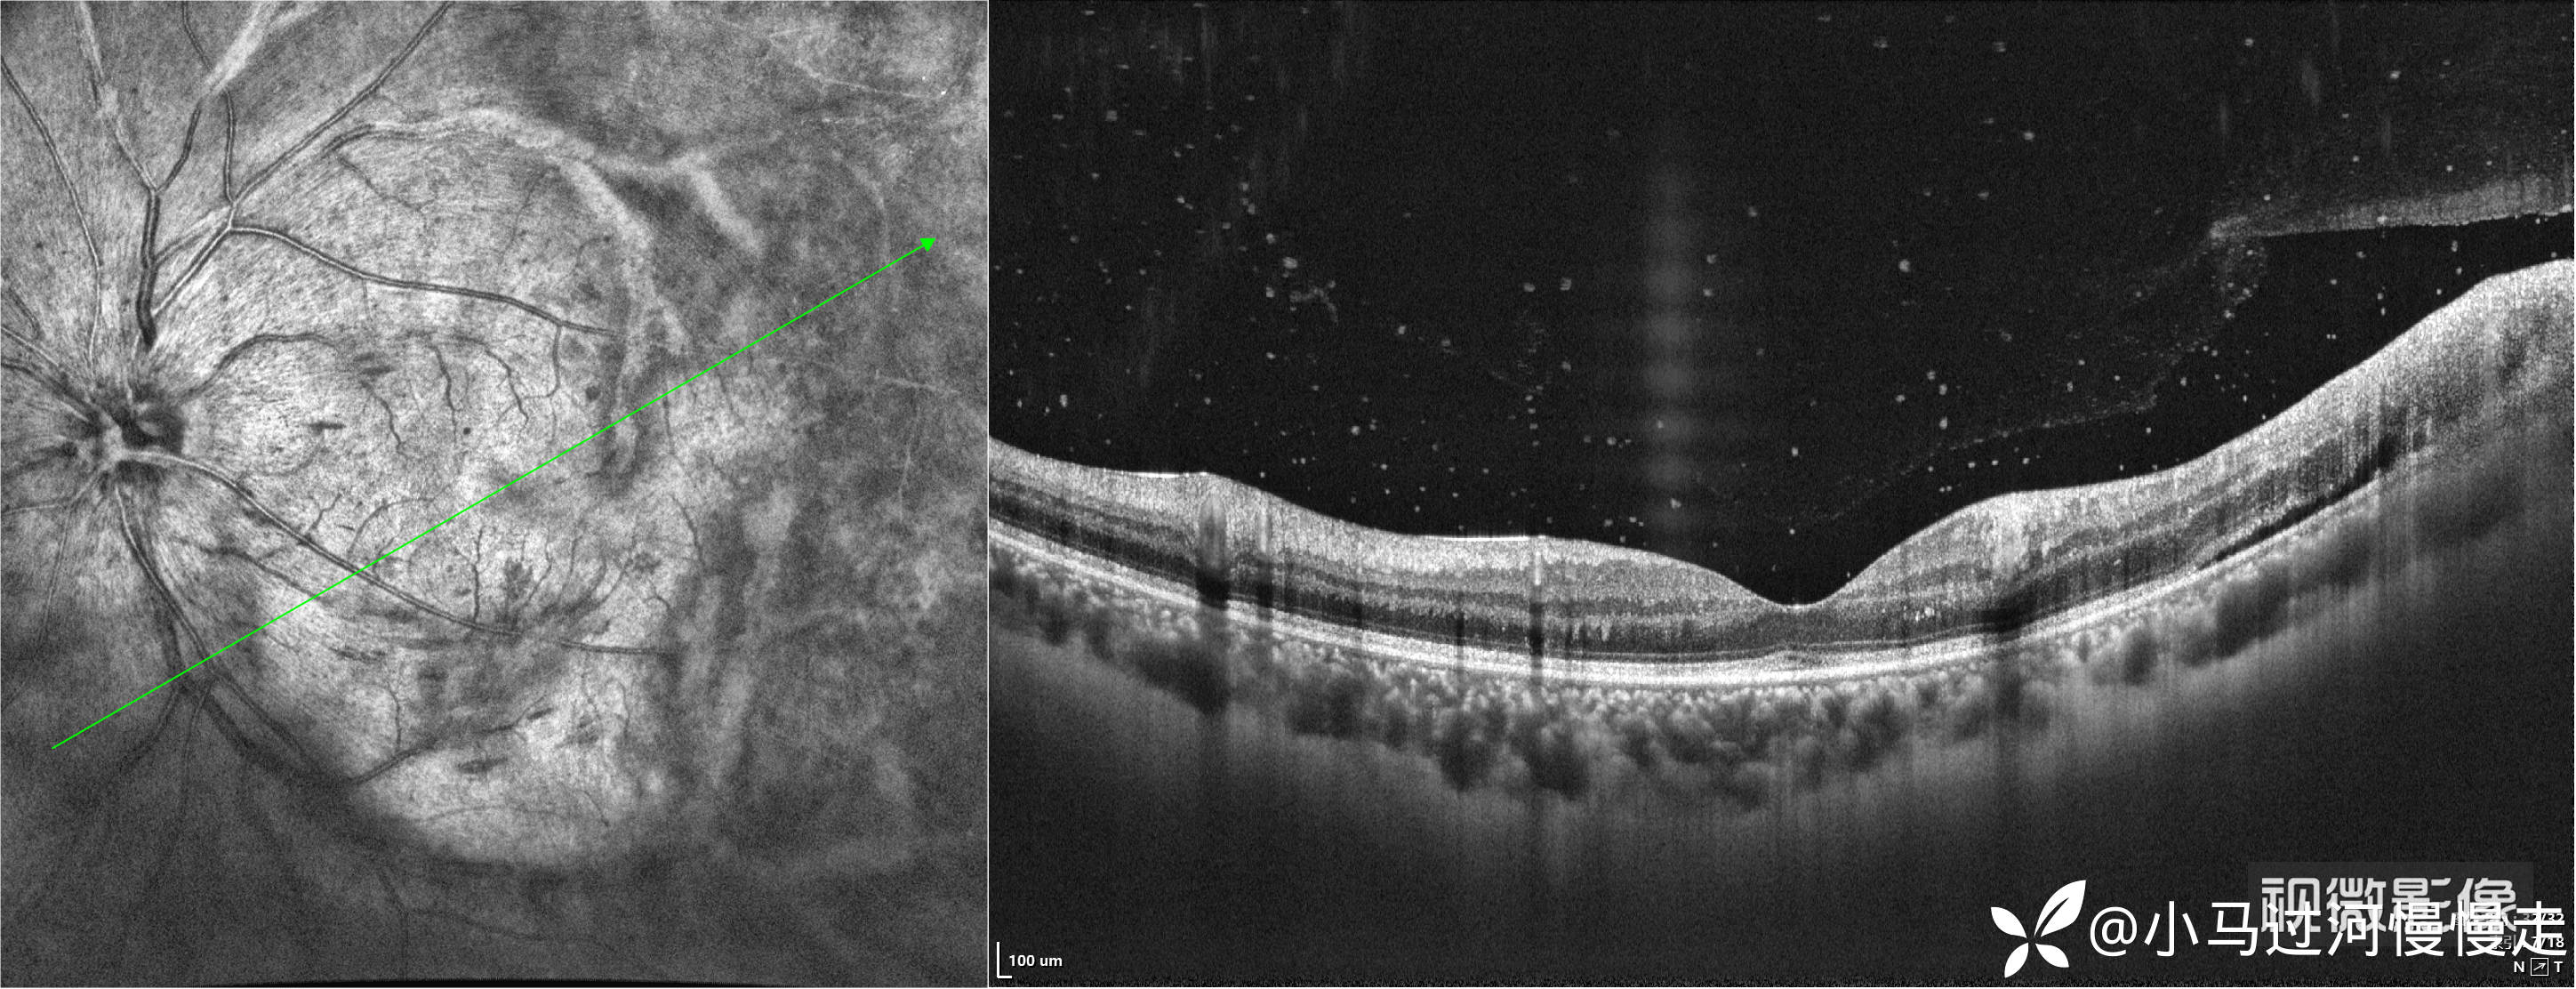

当时正在试用视微SSOCT,记录了左眼颞侧病变的影像。

依据患者AIDS病史,典型的眼部表现初步诊断了巨细胞病毒性视网膜炎(CMVR),后患者外院就诊确诊了CMVR,没有回来复查,这是我唯一见过的HIV合并CMVR的病例。